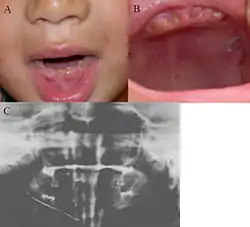

الأعراض السريرية متغيرة ، و لكن الأسنان التي عادة ما تكون مشمولة و متأثرة بقوة هي الأسنان اللبنية في النوع الأول، بينما في النوع الثاني الأسنان اللبنية و الدائمة مصابة بالتساوي. يكون لون الأسنان من رمادي إلى أصفر، و تظهر الأسنان بألوان شفافة و غميمة. في معظم الحالات تفقد المينا باكراً نتيجة لفقدان النتؤات الموجودة على الموصل السني المسنائي، و مع كل هذا فإن الأسنان ليست أكثر عرضة للتسوسفوق المعدل الطبيعي. بعض مرضى تكوُّن العاج المعيب سيعانون من تعدد خراج حوائط الذروة ، و التي تحدث نتيجة الانسداد اللبي أو الانكشاف اللبي الذي يكون سببه الاهتراء الكلي ؛ مما يؤدي إلى الاختناق اللبي، هؤلاء المرضى يحتاجون لجراحة قميه لإنقاذ الأسنان المتأثرة.[3]

سمات التصوير الإشعاعي

النوع الأول و الثاني يبيّنان انسدادًا كليًا في الحجرة اللبية، أما النوع الثالث يبين عاجًا رفيعًا جدًا و حجرة لبية هائلة، و تسمى هذه الأسنان بالأسنان الصدفية.